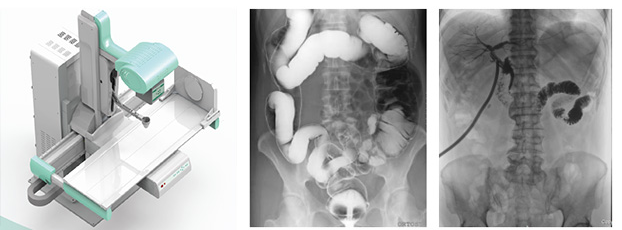

隨著現(xiàn)代醫(yī)療技術(shù)快速發(fā)展,傳統(tǒng)的X射線技術(shù)實(shí)現(xiàn)數(shù)字化,出現(xiàn)了多功能DR。多功能DR采用數(shù)字影像平板探測(cè)器取代傳統(tǒng)膠片,直接捕獲X線影像,并轉(zhuǎn)化為高清晰數(shù)字圖像,對(duì)比傳統(tǒng)的間接影像設(shè)備,多功能DR可以直接將X射線轉(zhuǎn)化成圖像,成像更清晰,放射劑量更小。

多功能DR大大提高了普通放射設(shè)備準(zhǔn)確診斷的能力,為臨床創(chuàng)造了價(jià)值,它可以進(jìn)行全身各部位的拍片、透視和點(diǎn)片攝影。接下來(lái)小編給大家介紹一下這三種模式的區(qū)別。

點(diǎn)片攝影是在透視的條件下,對(duì)病變部位進(jìn)行可視化觀察,待發(fā)現(xiàn)疑似病變部位的時(shí)候進(jìn)行瞬間點(diǎn)片,從而能夠準(zhǔn)確獲取病變部位的高清影像用于臨床診斷,從而在一定程度上降低漏診誤診率。病人不動(dòng),通過選擇鍵由透視直接切換攝影的曝光過程。在透視過程中,保存一幅靜止的圖像。常用于消化道、膽系造影下的攝影等。它既可以觀察運(yùn)動(dòng)器官的運(yùn)動(dòng)功能,又能在有感興趣的圖像時(shí),對(duì)膠片曝光保留感興趣的圖像,便于進(jìn)一步診斷。